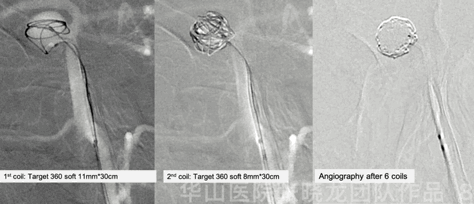

图 7. 基底动脉瘤测量:动脉瘤大小9.4*4.9mm,瘤颈7.6mm。一根Echelon-10微导管置于流出道用来保护小脑上动脉,另一根Prowler Plus微导管栓塞动脉瘤。

图 8 GIF. 经栓塞微导管 依次填入6枚弹簧圈( Target 360 soft 11mm*30cm, 8mm*30cm, 8mm*20cm, 7mm*30cm, 5mm*10cm, 5mm*15cm )。经Echelon-10微导管证实右侧小脑上动脉通畅。

图 9 GIF. 继续填入2枚弹簧圈,复查造影右侧小脑上动脉通畅,动脉瘤流入道少许残留( Raymond IIIb)。